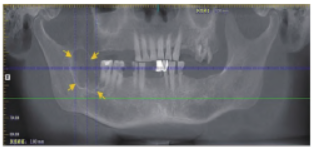

口腔曲面断层片(图1)示:右侧下颌升支前份可见一形状不规则的低密度影,边界不清晰,周围无骨白线,前至47牙根远中,后至右下颌升支中部,上至喙突下方,下至下牙槽神经管。口腔锥形束CT(cone beam CT,CBCT)矢状面(图2)示:右侧下颌升支内肿物侵犯骨质,可见大小不一多房间隔,颊、舌侧骨质不规则吸收缺如,边界欠清晰,并侵犯下牙槽神经管。

图1 术前影像学检查。箭头示右侧下颌骨升支区骨破坏病变。